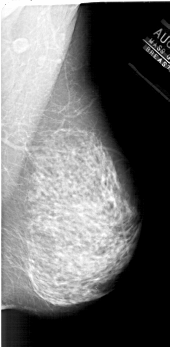

A_1878_1.RIGHT_MLO

RIGHT_MLO LINES 6241 PIXELS_PER_LINE 3046 BITS_PER_PIXEL 12 RESOLUTION 43.5 NON_OVERLAY